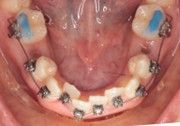

The left side shows a near-perfect 90° bend, created with maximum force using the IOS Mini Cinch Back Plier (not necessary, but Dr. Nielson wanted to test the upper limit).

Again, ideal bends were made very close to the bracket with the IOS Mini Cinch Back Plier, with no risk of dislodgement.